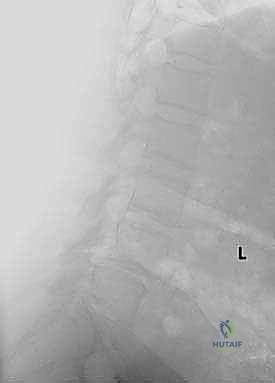

قبل الخوض في التفاصيل الدقيقة للعملية الجراحية، من الضروري والمهم جداً أن نفهم التشريح المعقد للعمود الفقري الذي نتعامل معه. إن العمود الفقري الصدري القطني هو منطقة انتقالية فريدة من نوعها في جسم الإنسان، حيث تلتقي الفقرات الصدرية (المرتبطة بالضلوع والتي توفر الاستقرار) بالفقرات القطنية (التي تتحمل معظم وزن الجسم وتوفر مدى حركة كبير). هذه المنطقة حيوية ومرنة، ولكنها للأسف أيضاً الأكثر عرضة للإجهاد الميكانيكي، والإصابات الرضية، والكسور.

المنطقة الصدرية القطنية (Thoracolumbar Junction): نقطة الضعف الميكانيكية

هذه المنطقة (من T11 إلى L2) تعتبر نقطة انتقال ميكانيكي حرجة. الجزء الصدري فوقها صلب ومقيد بالقفص الصدري، بينما الجزء القطني تحتها مرن ومتحرك. هذا الانتقال المفاجئ من الصلابة إلى المرونة يجعل هذه المنطقة عرضة بشكل غير متناسب للكسور الرضية (مثل كسور الانفجار بسبب حوادث السيارات أو السقوط من ارتفاع) والإجهاد الميكانيكي الذي يؤدي إلى الانزلاق الفقاري.